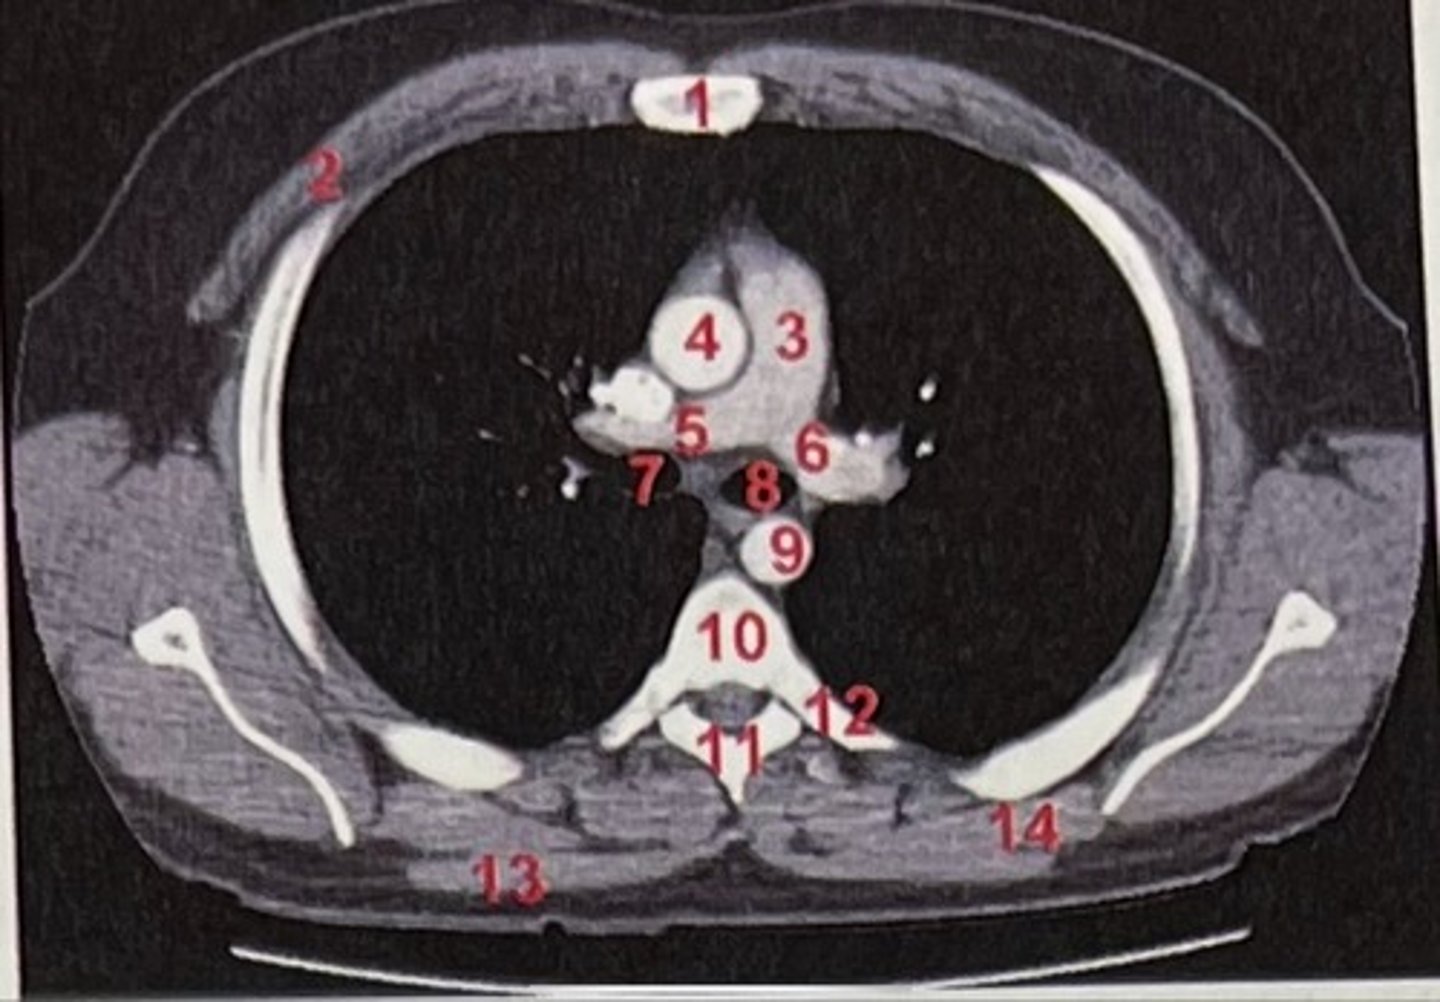

Sternum

What is 1

pectoralis major

What is 2

Pulmonary trunk

What is 3

Right and left pulmonary arteries

What is 5 and 6

Ascending aorta

What is 4

right primary bronchus, left primary bronchus

What is 7 and 8

Descending aorta

What is 9

Rhomboid major

What is 14